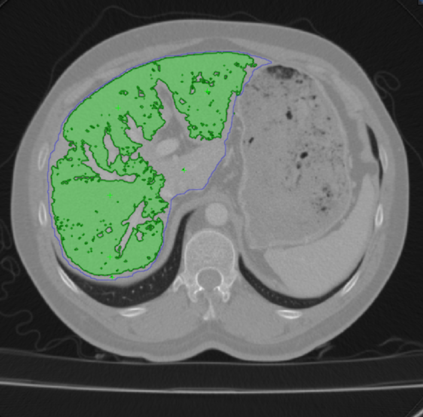

There are many approaches to weakly-supervised training of networks to segment 2D images. By contrast, existing approaches to segmenting volumetric images rely on full-supervision of a subset of 2D slices of the 3D volume. We propose an approach to volume segmentation that is truly weakly-supervised in the sense that we only need to provide a sparse set of 3D points on the surface of target objects instead of detailed 2D masks. We use the 3D points to deform a 3D template so that it roughly matches the target object outlines and we introduce an architecture that exploits the supervision it provides to train a network to find accurate boundaries. We evaluate our approach on Computed Tomography (CT), Magnetic Resonance Imagery (MRI) and Electron Microscopy (EM) image datasets and show that it substantially reduces the required amount of effort.